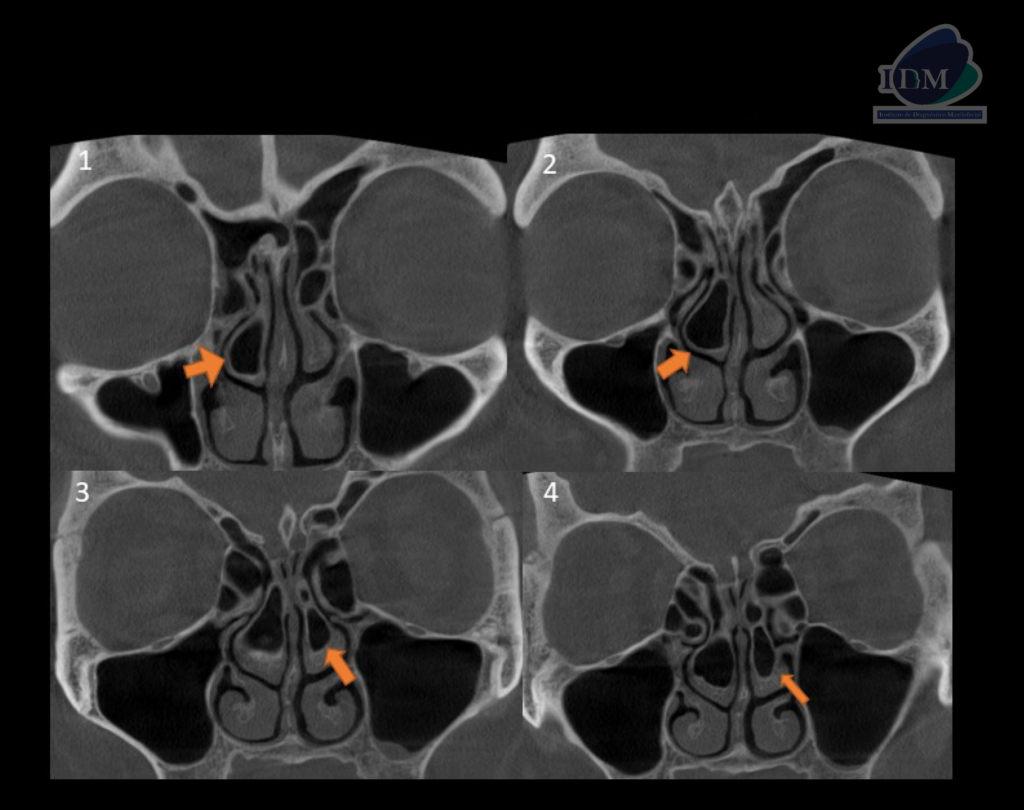

A la evaluación de la tomografía computarizada de macizo facial en los cortes axiales, coronales y sagitales se observa la neumatización de los cornetes medios a predominio del lado derecho que se presenta como una imagen hipodensa de forma irregular y limites definidos, asimismo se evidencia la presencia de un septo intrasinusal vertical a nivel de la porción media del cornete medio del lado derecho y la levodesviación del tabique nasal, signos imagenológicos compatible con concha bullosa.

CORTES CORONALES